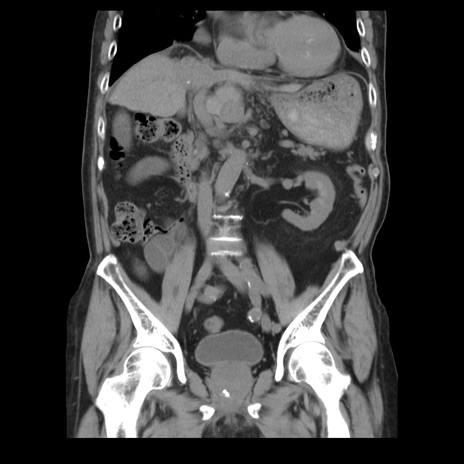

横断像

【症例】70歳代男性

【主訴】腹痛

【現病歴】肝硬変・肝細胞癌にてかかりつけの方。約9時間前に食後より腹痛出現。症状が徐々に増悪し、嘔吐出現したため来院。

【既往歴】肝硬変、肝細胞癌(RFA、TACE後)

【身体所見】意識清明、表情苦悶様、BT 36℃、BP 129/78mmHg、P 88bpm、SpO2 97%(RA)、右上腹部から心窩部にかけて圧痛あり、反跳痛なし、筋性防御あり。

【データ】WBC 5800、CRP 0.16